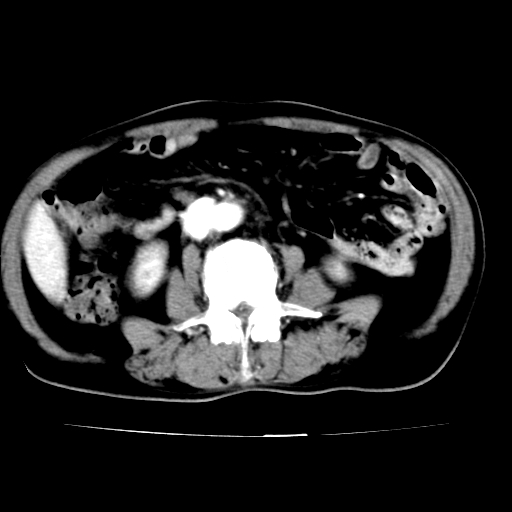

男,75岁,腹痛月余,彩超发现脐周腹主动脉异常回声。临床诊断:腹主动脉瘤。

ct诊断:右骼总动脉囊性动脉瘤并瘤内附壁血栓形成,与下腔静脉之间形成动静脉瘘。

腹主动脉分叉处真性动脉瘤,附壁血栓形成。

给平扫片看看血管壁钙化情况。

此病例平扫图像已发,请大家看看!